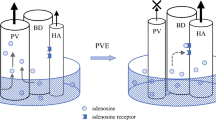

Numerous recent studies have reported on strategies for safe major hepatectomy. A historical landmark was the introduction of portal vein embolization (PVE) in the mid-1980s to induce hypertrophy of the FLR [5,6,7]. The introduction of the Makuuchi criteria, which are based on the indocyanine green retention rate at 15 min (ICG-R15) [8], in the mid-1990s facilitated the preoperative assessment of the liver function. Since the 1990s, various methods have been proposed to accelerate FLR hypertrophy and evaluate the function of the FLR before surgery. However, several issues remain unresolved or controversial in the preoperative planning for major hepatectomy, as summarized in Fig. 1 and reviewed in this article.

The ICG-R15 value, however, reflects the function of the TFLV but not that of the FLR, and whether or not a gain of FLR volume as a result of PVE is a true reflection of an improved FLR function remains unclear. Several studies have suggested that the FLR function increases before hypertrophy of volume is apparent on CT [49, 50]. Uesaka et al. measured the biliary ICG concentration from multiple biliary drainage tubes placed for draining the entire liver in 8 patients who underwent right PVE and reported that the ratio of ICG excretion in the FLR to ICG excretion in the whole liver increased 20% on average after PVE, while the FLR/TFLV ratio increased only 8% on average [49].

Should PVE or ALPPS be used to induce hypertrophy of the FLR?

Another key question is whether PVE or ALPPS is superior for ensuring an adequate FLR for two-stage hepatectomy. Initially PVE was performed mostly in patients with hilar cholangiocarcinoma [5]. As the indications for hepatectomy for CRLM expanded to include even advanced bilobar disease, the use of major hepatectomy and, in parallel, the use of PVE increased remarkably [72, 73]. Furthermore, the development of chemotherapy contributed to the improvement of the prognosis after hepatectomy [74].

Considering the rather high rate of complications of ALPPS, including biliary fistula after the first-stage operation and PHLF after second-stage hepatectomy, routine application of ALPPS for extensive disease is not yet warranted; PVE, a less-invasive method for inducing FLR hypertrophy, cannot be replaced with ALPPS. The use of spherical microspheres as embolization material or additional embolization of segment IV for extended right hepatectomy may enhance PVE-induced FLR hypertrophy [87]. The median hypertrophy rate of segments II and III after embolization of the right portal vein and segment IV branches exceeded 50% [88, 89]. The combination of PVE with transarterial chemoembolization is also effective, especially in patients with HCC [90, 91]. Furthermore, liver venous deprivation combining PVE with ipsilateral hepatic vein embolization, first reported by Nagino et al. [92] and recently increasingly frequently reported [93,94,95], shows promise. In these studies, although the interval until hepatectomy was 3 to 4 weeks, the degree of hypertrophy [96] or kGR was higher after liver venous deprivation than after PVE alone, and there were few procedure-related or postoperative severe complications. Rapid functional recovery was also confirmed using hepatobiliary scintigraphy [97]. LVD may therefore be a new and safe approach for optimizing liver regeneration before major hepatectomy [98].